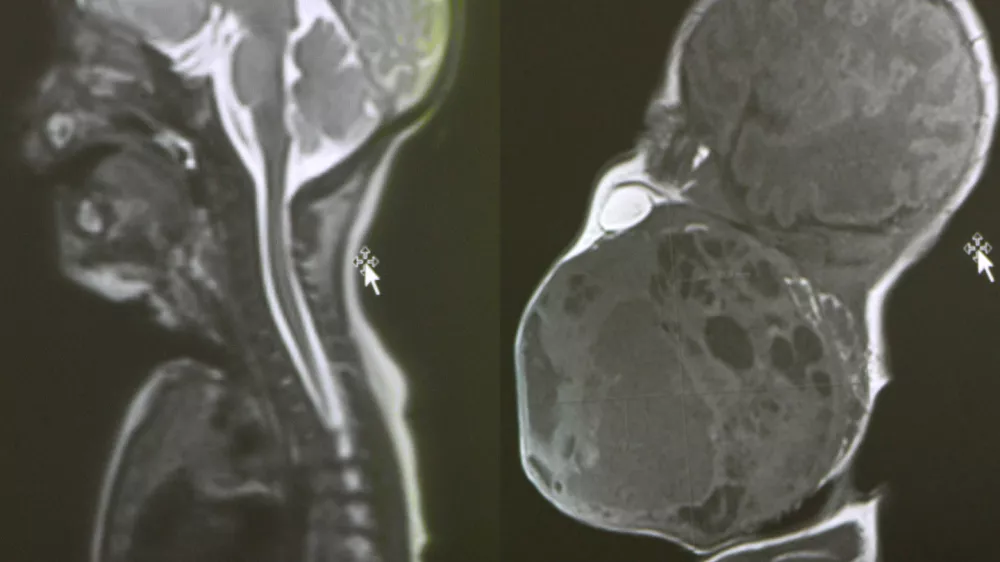

V zagrebški bolnišnici Rebro so izvedli izredno zahtevno operacijo, s katero so novorojenčku rešili življenje. Med carskim rezom so porodili le glavo, vrat in del prsnega koša dojenčka, preostanek telesa pa je ostal v maternici, da je otrok še naprej prejemal kisik prek posteljice. Tako je ekipa pridobila dragocene minute za odstranitev tumorja. Novorojenček je imel namreč na vratu ogromen tumor, velik kot še ena glava, ki je zapiral njegovo dihalno pot.

Nekaj ur po rojstvu je sledila zahtevna operacija dokončne odstranitve tumorja, ki je trajala več kot dve uri. Prof. dr. Drago Prgomet je povedal, da je bil cilj postopka odstraniti tumor in ohraniti vse vitalne funkcije – dihanje, požiranje in kasnejši govor. Histološka analiza je potrdila, da je bil tumor v celoti odstranjen, tumorski markerji pa so negativni. Otrok je ozdravljen, vendar ga bodo prva tri leta preventivno še spremljali.